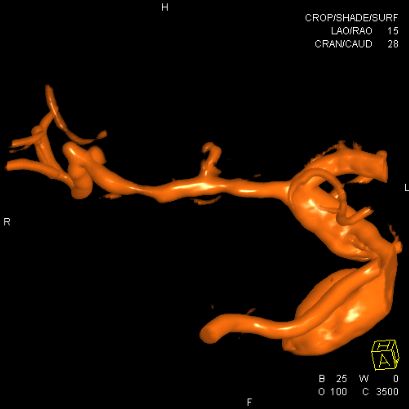

确认为夹层,直接支架植入

远端似乎打开不好,由于确认了为夹层,后面支架会进一步打开,无需过多操作,进一步球扩可能会导致高灌注,因为MCA远端的上干已经闭塞,只有下干,手术保留豆纹动脉的通畅为重点

支架进一步打开,直径改善到2.9mm

进一步打开的支架的形态,打开满意